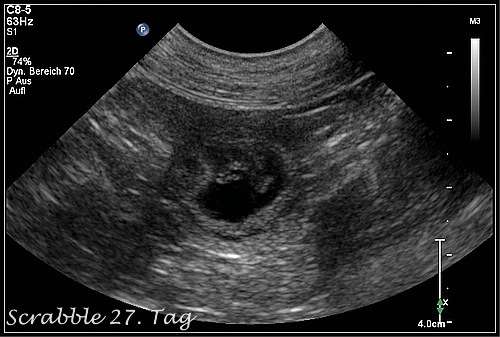

Tag 27 der Trächtigkeit

Heute am 15.09.2017waren wir zum Ultraschall. Es hat sich bestätigt: Scrabble ist trächtig. Die Augen und die Nervenstränge im Rückenmark werden gebildet. Die Organbildung beginnt. Die Embryonen sind etwa walnussgroß.